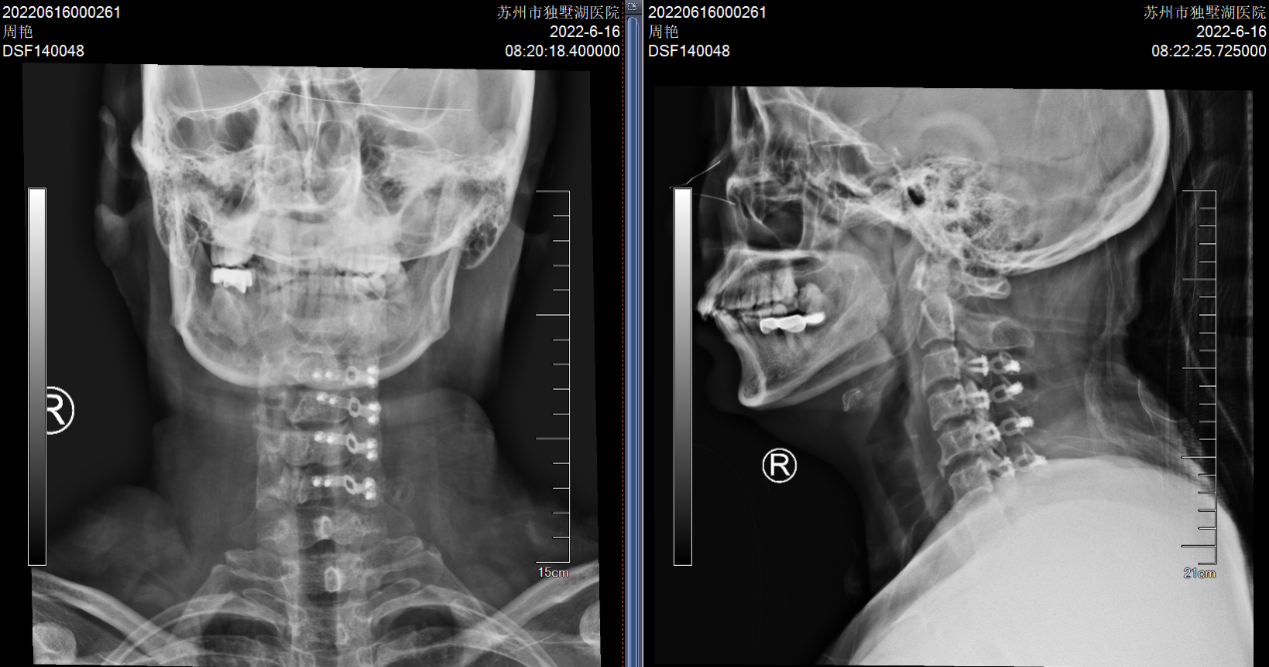

(颈椎术后X片:C3-6椎管扩大成形术后)

(C5-6 ACDF术,患者手术疗效确切)